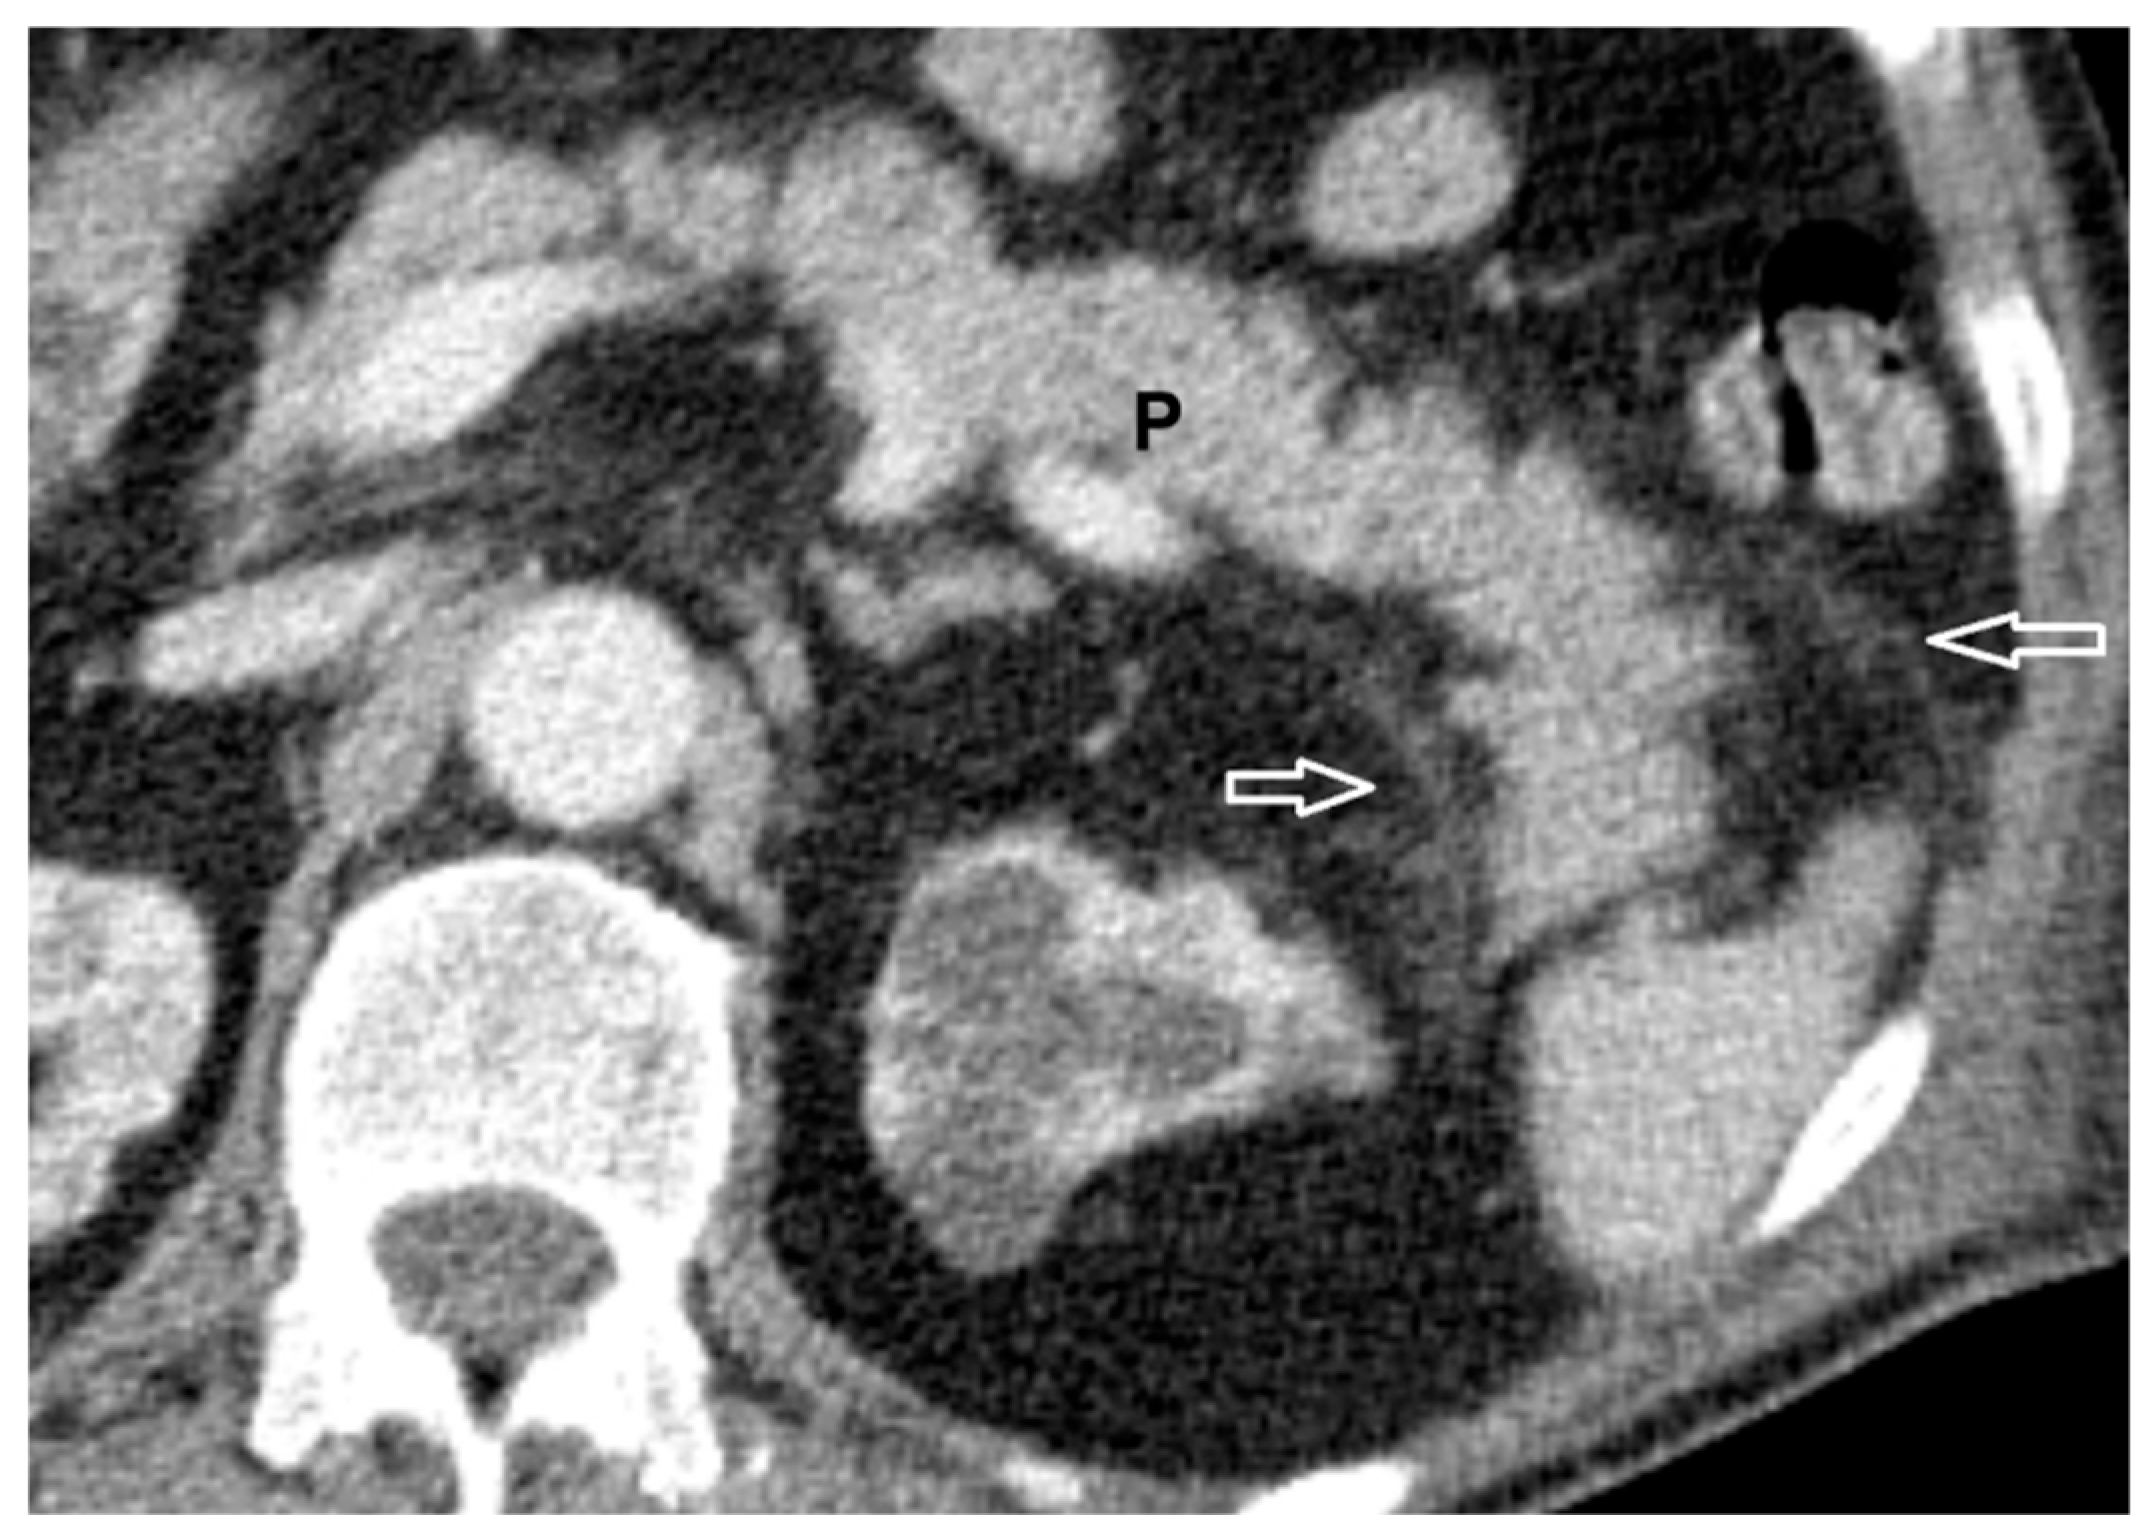

- diffuse or focal enlargement of the pancreas → 1;

- minimal peripancreatic changes → 2;

- single peripancreatic fluid collection → 3;